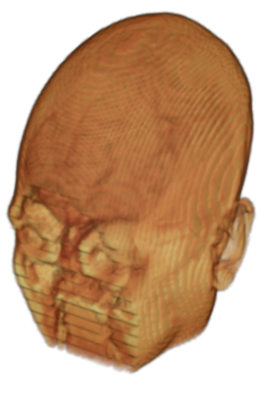

To prevent these types of attack, medical scans are currently de-identified using crude removal-based techniques [Bischoff-Grethe et al.(2007)Bischoff-Grethe, Ozyurt, Busa, Quinn, Fennema-Notestine, Clark, Morris, Bondi, Jernigan, Dale, Brown, and Fischl, Schimke et al.(2011)Schimke, Kuehler, and Hale, Milchenko and Marcus(2013)] which seek to remove privacy-sensitive parts of the head (examples in Figure 3). However, as we demonstrate, these existing techniques fail to reliably hide the patient’s identity – or they are so aggressive that they impair further medical analyses. A better solution is needed.

Benchmark De-Identification Methods. We compare our result with three publicly available and widely-established methods for de-identification of MRI head scans, depicted in Figure 3. All methods have in common that they (1) are not deep-learning-driven, (2) require no additional training and (3), are used on a day-to-day basis in neuroscience and clinical research. All procedures were applied with default settings on images of resolution . The methods include QUICKSHEAR [Schimke et al.(2011)Schimke, Kuehler, and Hale], FACE MASK [Milchenko and Marcus(2013)], and DEFACE [Bischoff-Grethe et al.(2007)Bischoff-Grethe, Ozyurt, Busa, Quinn, Fennema-Notestine, Clark, Morris, Bondi, Jernigan, Dale, Brown, and Fischl]. Descriptions of the methods are provided in the Appendix. We also include MRI WATERSHED [Ségonne et al.(2004)Ségonne, Dale, Busa, Glessner, Salat, Hahn, and Fischl], a skull-stripping method that removes everything except the brain.